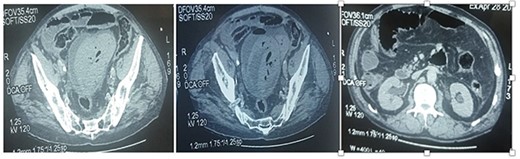

The CT scan showed a full bladder with multiple dense, declining formations, with air bubbles in their breasts, not enhanced after injection of contrast medium. It is also the site of a dense, heterogeneous, non-decreasing formation at the level of its dome, with multiple air bubbles within it, protruding at the level of the peritoneal fat opposite the dome with parietal defect. Presence of a subperitoneal effusion with hydroaerobic levels in the bladder. Presence of a pneumoperitoneum of medium abundance with diffuse infiltration of the mesenteric fat (Fig. 1). The decision to refer to the operating room (OR) and explore was made.

CT images showing a deformed bladder with the presence of a hematoma and air bubbles and from the contents to the dome lateralized to the left. Pneumoperitoneum with peritoneal effusion.